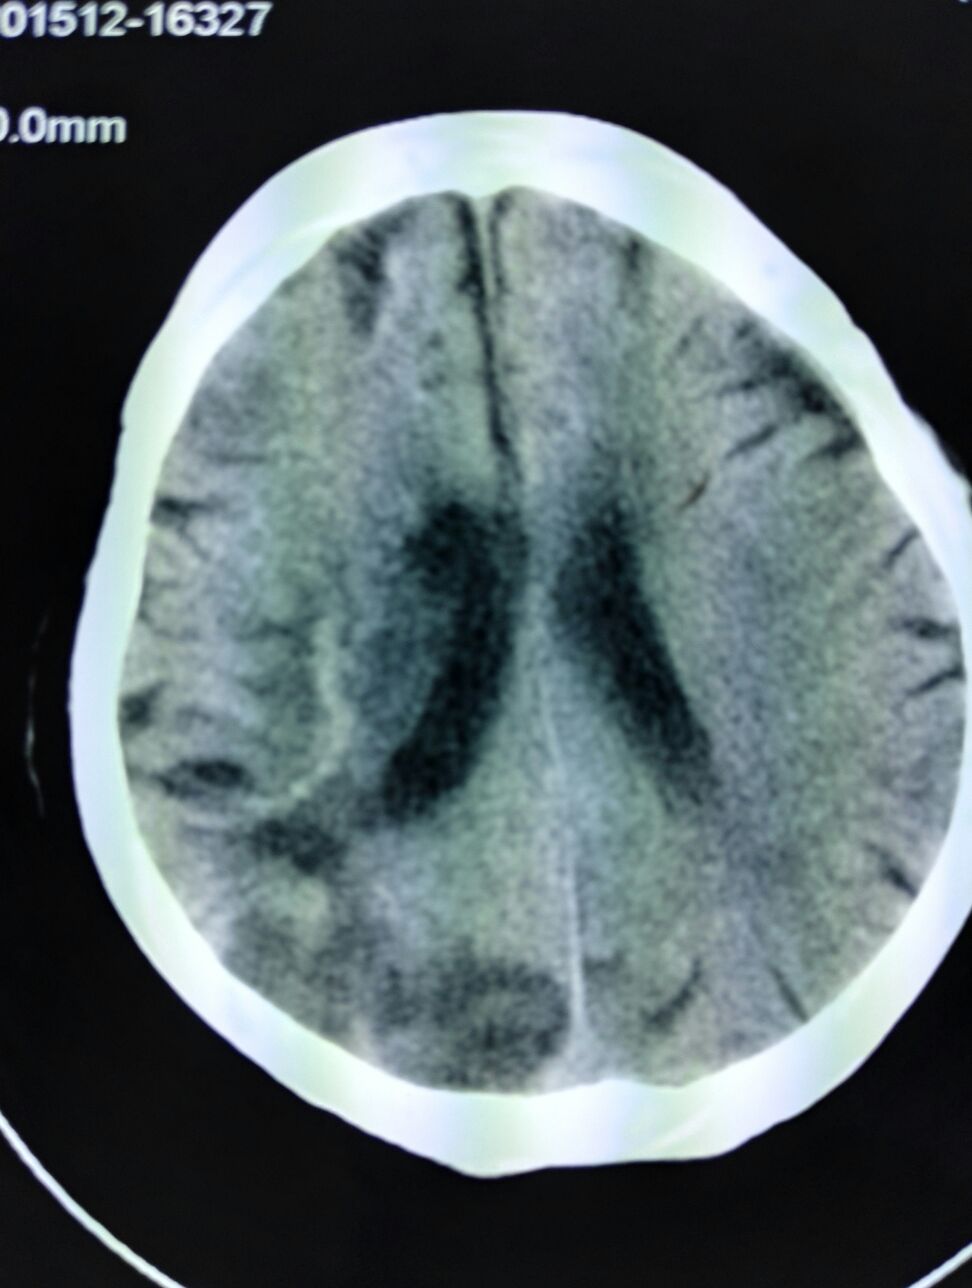

老年男性,主诉,活动后胸片气喘伴左侧肢体无力一天入院。既往史,有心律不齐房颤心衰,病史多年,平时口服螺内酯,依那普利。等药物治疗。入院查体,期为36.8摄氏度,89次,每分钟双肺呼吸音清,心率89分钟,心律不齐,脉搏短绌,第一心音强弱不等,双下肢轻度浮肿,并伴左侧肢体无力,作头颅ct示脑栓塞。住院后给于抗炎抗凝活血化瘀营养脑细胞治疗治疗几年后症状缓解,请问大家,房颤引起的脑栓塞,氯吡格雷,可以预防脑栓塞吗?

患者老年女性,主因,左侧肢体偏瘫8小时收入,既往房颤史,查体,血压180/90mmhg神情,言语不清,饮水呛咳,双侧瞳孔等大同圆对光反射灵敏,双肺呼吸音粗,心率82次/分律不齐,心音强弱不等,各瓣膜区未闻及病理性杂音,腹部无异常,左侧肢体肌力0级,肌张力不高,右侧肢体肌力正常,左巴氏征阳性